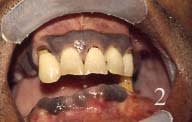

2-Pigmentation raciale

Essentiellement due à la mélanine